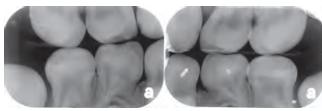

Eruption cyst (EC) | Dentigerous 萌發 | 12a, 12b, 34a, ?6 | 10y ↓ | 藍色或紫棕色 ![]() ![]() |

|